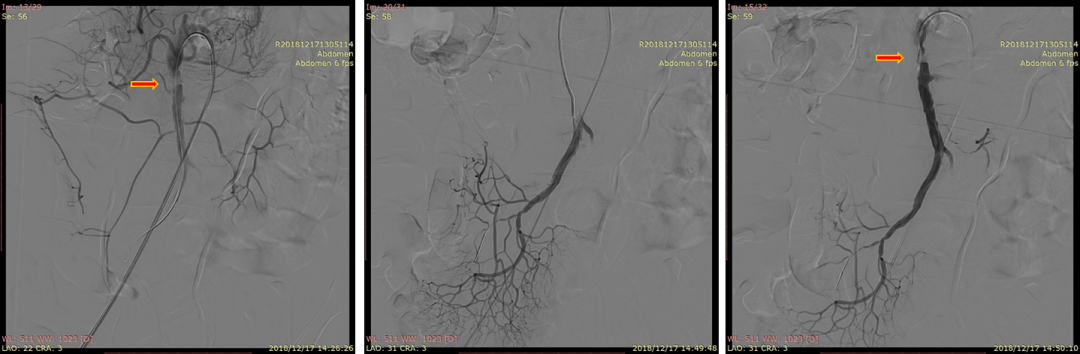

20181217DSA:找到远端真腔血流受限的原因(箭头)

20181217DSA:支架植入后最终复查造影

有的研究者把ISMAD影像学特征用于选择腔内支架治疗的标准,如在疑似肠道缺血的基础上,真腔狭窄80%或假腔动脉瘤直径>2cm;随访期间夹层动脉瘤直径>2cm或假腔溃疡型结构的扩大,这些作为腔内支架治疗的标准。但文献报道夹层动脉瘤破裂至今仅数例,临床随访症状缓解的病人,未见假腔快速扩张。

文献所列举的腔内治疗方式,主要是指肠系膜上动脉支架植入术,极少数采用单纯球囊扩张及采用弹簧圈栓塞假腔。从解剖角度看,肠系膜上动脉胰腺后段是好发裂口的部位,也是比较固定的部位,会受到牵拉力的冲击,因此在植入支架时,应考虑将支架跨过裂口的近端,且完全覆盖血管的胰腺后段,以减少支架移位或缩短的可能。